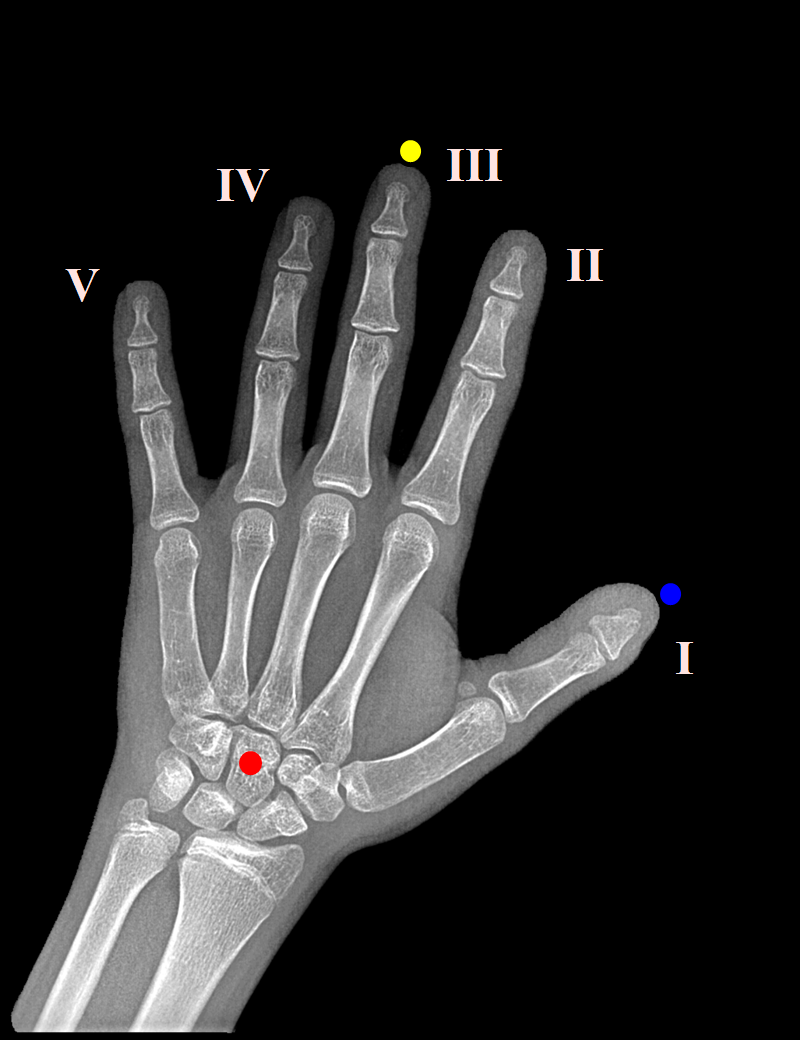

В качестве ключевых точек были выбраны кончик среднего пальца, центр головчатой кости в запястье (Capitate), кончик большого пальца. Вручную были размечены 800 снимков. Почему-то оказалось сложно найти рабочий софт для такой простой задачи как разметка точек, но в итоге нашёлся и отлично подошёл VGG Image Annotator (VIA). Снимки были приведены к размеру 2080x1600 и в процессе тренировки отмасштабированы с 16-кратным уменьшением.

Когда ключевые точки найдены, остаётся посчитать аффинное преобразование (масштабирование, поворот, сдвиг и кое-где зеркальное отражение), чтобы кончик среднего пальца и головчатая кость оказались на одной вертикали, 100 пикселей сверху и 480 снизу соответственно, а большой палец справа: